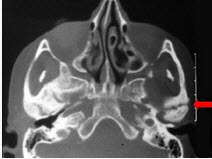

227、单项选择题

60岁男性,左耳垂下无痛性肿物缓慢长大四年,局部有胀感。检查见肿块位于腮腺后下极,表面光滑,质中偏软,不可压缩,与皮肤无黏连。影像检查结果如图

。最可能的诊断是()

A.腮腺多形性腺瘤

B.腮腺沃辛瘤

C.腮腺内淋巴结炎

D.腮腺血管瘤

E.腮腺囊肿

228、多项选择题 关于颊粘膜癌描述正确的是()